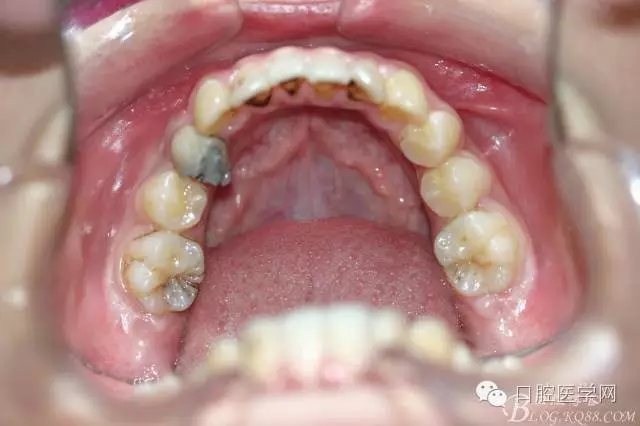

正畸前照片:

正畸后照片: